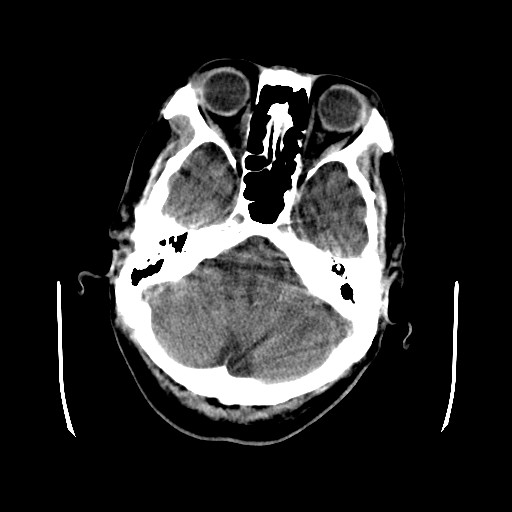

患者,男,70岁,清晨(10小时前)无法自行起床,家人无法唤醒,现昏迷,大小便失禁

左颞枕叶交界区可见类圆形高密度区,边缘可见环形更高密度影,并夹杂有点状钙化影,占位效应明显,未见明显水肿影,考虑脑膜瘤出血

左颞枕叶交界区可见类圆形高密度区,边缘可见环形更高密度影,侧脑室后角明显受压而周围未见明显水肿.考虑脑膜瘤伴出血可能性大不排外血管畸形.建议mr进一步检查.

左侧颞枕叶交界区见类圆型等高密度混杂影,边缘可见高密度影环绕,同侧侧脑室后脚受压变形,周边围见明显水肿影. 结论:脑膜瘤首先考虑.

左颞枕叶交界区的类圆形高密度区首先考虑脑膜瘤卒中,病人左侧小脑半球的还有多个囊性低密度,要考虑同时伴有梗塞的可能。